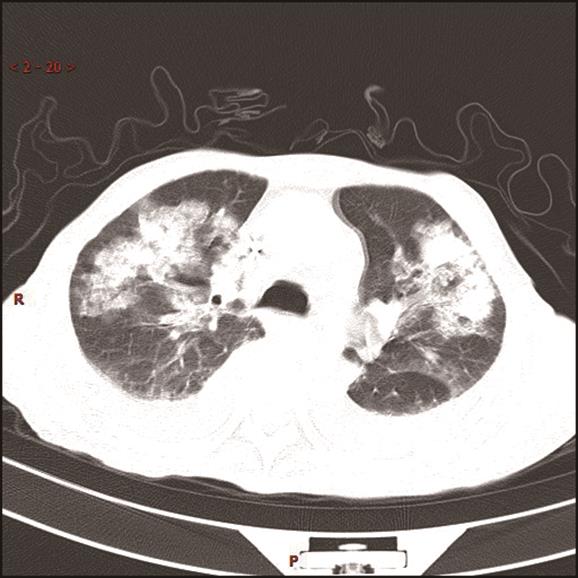

• 基于宏基因组二代测序诊断15例鹦鹉热衣原体肺炎临床特征与诊治分析

2023, 48(6):715-720. DOI: 10.13406/j.cnki.cyxb.003248

摘要 (49) HTML (29) PDF 858.28 K (202) 评论 (0) 收藏

摘要:目的 探讨和分析少见鹦鹉热衣原体肺炎的临床特征、诊治及预后,以期提升临床相关学科领域对该病的认识。方法 回顾性研究赣南医学院第一附属医院2017年1月至2022年12月确诊的15例鹦鹉热衣原体肺炎患者的临床资料,总结并分析该病的临床特征、诊断与鉴别要点,同时检索国内外文献资料对鹦鹉热衣原体肺炎的最新诊疗进展予以系统性讨论。结果 纳入本研究的15例鹦鹉热衣原体肺炎患者中,男性10例(66.67%),女性5例(33.33%),年龄62(32~79)岁,禽类接触史14例(93.33%),基础疾病史8例(53.3%),转化为重症肺炎5例(33.33%)。15例患者中,白细胞计数(white blood cell count,WBC)正常8例(53.3%),WBC升高5例(33.3%),WBC减低2例(13.3%);血红蛋白(hemoglobin,HGB)正常9例(60.0%),减低6例(40.0%);中性粒细胞百分比(neutrophils,NE)升高13例(86.7%);所有患者(100.0%)C反应蛋白(C-reactive protein,CRP)均显著升高;13例(86.67%)患者降钙素原(procalcitonin,PCT)升高;12例(80.0%)患者乳酸脱氢酶(lactate dehydrogenase,LDH)升高;11例(73.33%)肝功能异常;8例(53.33%)肾功能异常;6例(40.0%)凝血功能异常;13例(86.7%)电解质紊乱。此外,11例(73.33%)患者动脉血气分析显示不同程度血氧分压降低,8例(53.33%)氧合指数(oxygenation index,OI)低于300 mmHg,4例(26.67%)患者无明显呼吸困难,未进行动脉血气分析检查。本研究所有患者均已完善经支气管镜检查,并获取支气管肺泡灌洗液(bronchoalverolar lavage fluid,BALF)行宏基因组二代测序(metagenomic next-generation sequencing,mNGS)检测,检出的病原体除鹦鹉热衣原体外,所有患者均合并多种病原体感染。15例患者均已完善肺部电子计算机断层扫描(computed tomography,CT)等影像学检查,单侧肺部实变7例(46.67%),双侧实变8例(53.33%);9例(60.0%)患者伴有胸腔积液,部分患者可以表现出多种影像学表现,包括实变影、磨玻璃影、团块样实变影、反晕征、纵隔和肺门淋巴结肿大等。15例鹦鹉热衣原体肺炎患者在确诊后均予规范抗感染治疗,其中5例重症肺炎患者中2例患者予体外膜肺氧合(extracorporeal membrane oxygenation,ECMO)辅助治疗,所有患者均未见治疗相关不良反应或不良事件,平均住院日为13.9 d。本研究所有患者未见死亡,均好转出院。结论 鹦鹉热衣原体肺炎临床特征及表现缺乏特异性,易出现重症化,经支气管肺泡灌洗液予mNGS检测可精准确诊,早期予四环素类及喹诺酮类抗生素可最大程度改善患者预后。